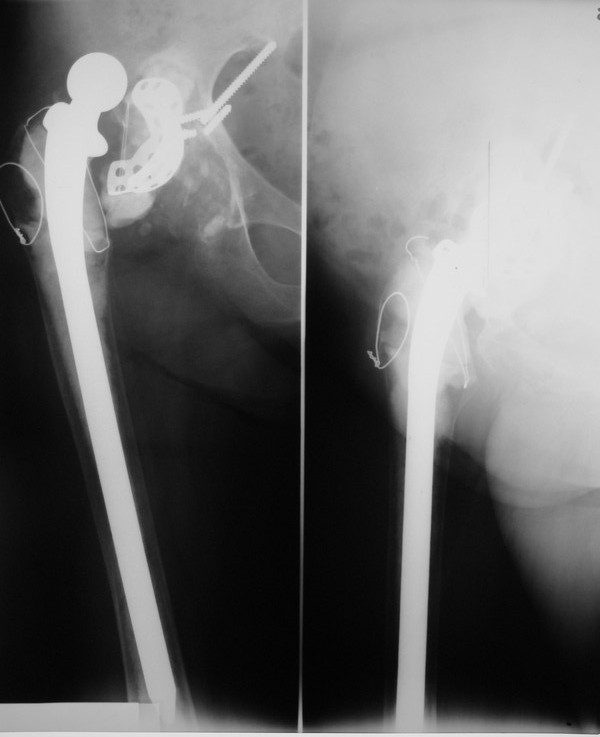

Уважаемые коллеги,в клинику поступила пациентка 51год с нестабильным антипротрузионным кольцом и вывихом эндопротеза. В течени длительного времени у пациентки ревматойдный полиартрит с приемом преднизолона. В 1994 году произведено эндопротезирование правого тазобедренного сустава бесцементным эндопротезом Biotronic. В 2000году по поводу нестабильности эндопротеза проведено ревизионное вмешательство-удаление чашки и ножки, некрэктомия. Установка антипротрузионного кольца, цементной чашки и ревизионной цементной ножки Beznoska. В 2007году выявлена клиникорентгенологическая картина нестабильности кольца. В 2008году пациентка упала, произошел вывих эндопротеза и дислокация кольца с переломом винтов. Планируем ревизионное вмешательство-удаление кольца, чашки, винтов, пластика верхнего края вертлужной впадины массивным аллотрансплантатом с последующей установкой антипротрузионного кольца типа Burch-Shneider. Прошу коллег занимающихся ревизионным эндопротезированием высказать свое мнение.PS:у больной в 1998 году установлен цементный эндопротез Beznoska левого тазобедренного сустава и в 2003 году установлен цементный эндопротез De Puy LCS правого коленного сустава.